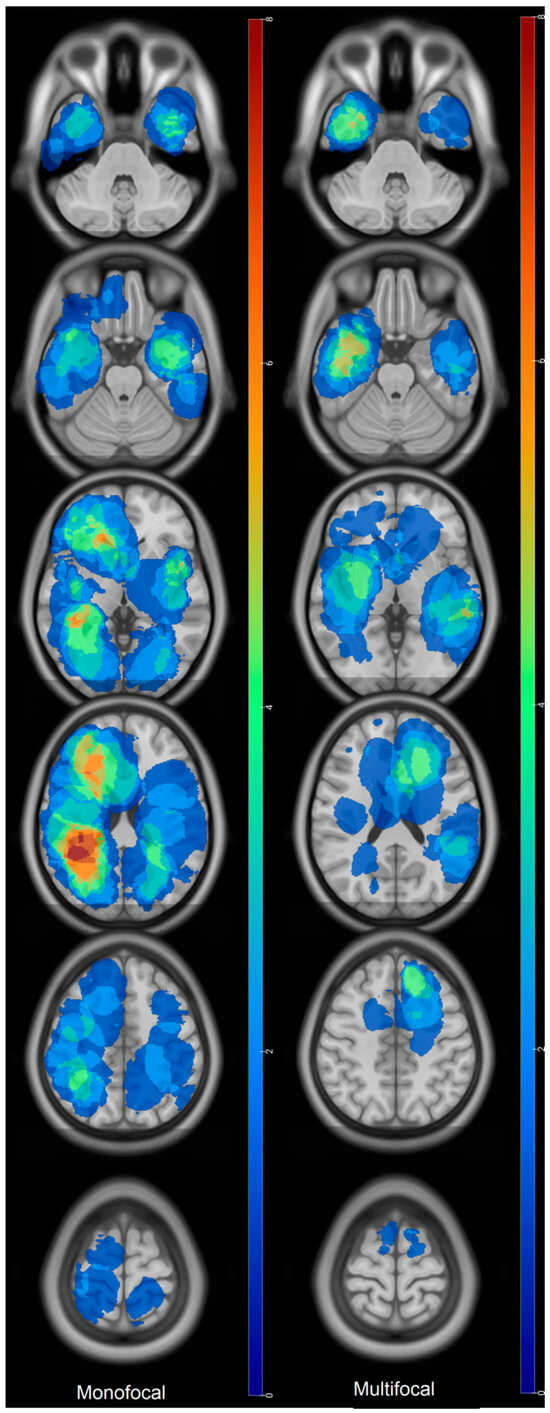

Prognostic Factors of IDH Wild-Type Glioblastoma After Extensive Surgery: A Multimodal Atlas of Tumor Locations, Recurrences and Management

by Hajar Selhane, Tiphaine Obara, Guillaume Vogin, René Anxionnat, Guillaume Gauchotte, Luc Taillandier, Marie Blonski and Fabien Rech

Cancers 2026, 18(1), 63; https://doi.org/10.3390/cancers18010063 - 24 Dec 2025

Introduction: Glioblastomas have poor prognosis despite aggressive treatment. Patterns of recurrence and overall survival (OS) can be very different. The population with complete resection having a so-called good prognosis can nevertheless present poor OS. Our purpose was to assess the OS and patterns [...] Read more.

Introduction: Glioblastomas have poor prognosis despite aggressive treatment. Patterns of recurrence and overall survival (OS) can be very different. The population with complete resection having a so-called good prognosis can nevertheless present poor OS. Our purpose was to assess the OS and patterns of recurrence thanks to multimodal statistical maps in glioblastoma with large extent of resection (residue < 10 mL). Methods: adult patients presenting IDH wild-type glioblastoma between 2013 and 2019 were selected. Clinical data and MRI characteristics were collected. Preoperative, postoperative, and recurrence volumes were segmented and normalized in the MNI space to compute statistical maps. Log-rank test and Cox model were used to assess OS and prognosis factors. Results: 60 patients were included. Mean residual volume was 0.89 ± 2 mL. Median OS was 22.3 months (95% CI: (20–35)). Initial location in the corpus callosum was associated with low OS (317 vs. 783 days, HR = 0.46, p = 0.003). At recurrence, KPS > 90 and tumor volume < 10 mL were associated with higher OS (p =0.006 and p = 0.05). Tumor contact with the SVZ as well as multifocal recurrence did not show any impact on the OS. Conclusions: High OS can be obtained thanks to surgery with residual volume < 10 mL. Invasion of the corpus callosum at diagnosis is associated with a poor prognosis despite a large extent of resection. Results suggest that large resection near the SVZ might decrease its putative influence on OS. Full article

Show Figures

Figure 1